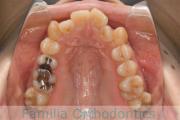

No.17V-474

- 主な症状:

- 上顎前突

- その他の症状:

- 過蓋咬合

- 年齢:

- 22歳

- 性別:

- 男性

- 抜歯部位

- 上:

- non

- 下:

- 88

- 主な使用装置:

- Invisalign

- 治療にかかった費用:

- 25万円

出っ歯を治したいということで小学生の時に来院されました。小学校高学年でヘッドギアを使って奥歯の位置を整えて、二期治療ではマウスピース型矯正装置のひとつ、インビザライン/Invisalign®(薬機法および医薬品副作用被害救済制度の対象外)を使用して治療を行いました。約1年半、20回程度の通院が必要でした。

- ≫治療前

-

上顎

下顎